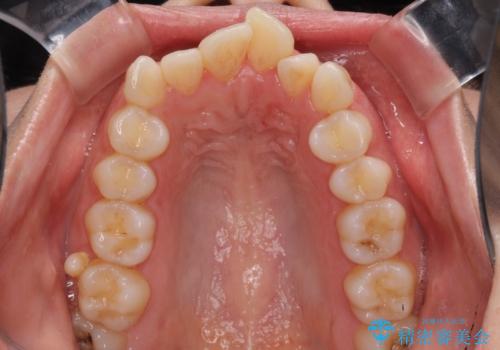

- 前歯のデコボコと口元の突出感を気にして来院された患者様です。

上下左右第一小臼歯4本を抜歯し、ワイヤー装置にて口元を引っ込めるよう矯正治療を行うこととしました。

叢生が強かったため、口元の突出感の改善には限界がありましたが、横側からも口元が引っ込んだ感じが分かるほど改善されました。